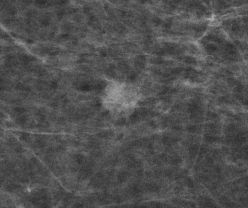

Mammografie-Screening-Programm: Brustkrebssterblichkeit könnte weiter gesenkt werden

Auswertung zeigt eindrucksvoll, dass die Teilnahme am Screening die

Brustkrebssterblichkeit um 20 bis 30 Prozent senkt. Damit wird bestätigt,

was die Wissenschaft seit Jahren beobachtet – Brustkrebsfrüherkennung

rettet Leben.